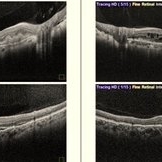

Both Eyes OCT in Case of CNVM with Angioid Streaks Both Eyes OCT in Case of CNVM with Angioid StreaksNov 29 2024 by Anand Temkar A 45 year old male came with chief complaint of blurring vision in right eyes since past 4 days. His vision is 6/12 in right eye and 6/9 in left eye. His vision was 14 mmHg in right eye and 16 mmHg in left eye. He was diagnosed with Angioid Streaks in both eyes about a year ago, then he developed choroidal neovascularization in his left eye 8 months ago, for which he received AntiVEGF injections x 3. Left eye is a stable eye now. Patient presented with right eye choroidal neovascularization in a case of Angioid Streaks on recent follow up. We have advised him right eye AntiVEGF injections x 3. In this image we can see the subretinal hyperreflective material in right eye and in left eye few cystic spaces are noted. Photographer: Dr.Anand Temkar- Retina Foundation, Ahmedabad Imaging device: Mirante Condition/keywords: Angioid Streaks, choroidal neovascular membrane (CNVM)